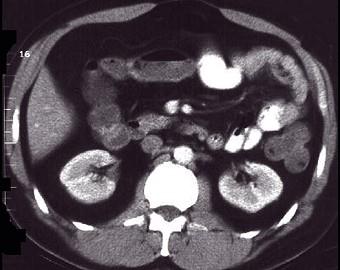

问题 女,30岁,右下腹痛,腹泻便秘交替出现,消瘦乏力,血沉加快,X线检查如图,最佳的诊断是 ( )

选项 A.小肠癌 B.小肠结核 C.小肠克罗恩病 D.结肠癌 E.阑尾炎

答案 C